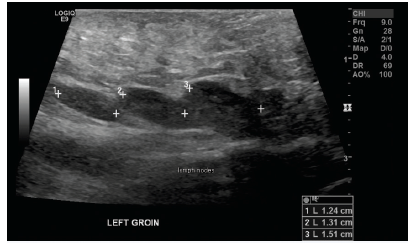

Jeffrey W. Taub, MD; Muhammad Ubaidulhaq, MD; Samie Ullah Ahmed, MD

A 17-year-old African American boy with sickle cell disease was admitted to the emergency department with a 4-day history of sharp, stabbing abdominal pain and lower back pain.